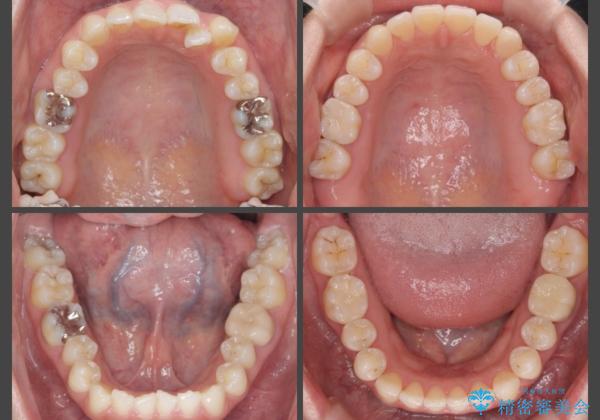

[ 歯並びと虫歯治療 ] 矯正治療とセラミック治療の包括治療

- 20代女性

- インビザライン

- 矯正治療と銀歯を外してのセラミック治療を当院で行いたいと希望され来院されました。

歯並びの改善に対しマウスピース矯正インビザラインシステムを、矯正治療後に銀歯を除去し精密なセラミックインレー治療を行い審美面の改善も含めた治療を計画します。

- 88万円 (矯正治療) 23.1万円(セラミックインレー×3)費用は治療当時の料金となります